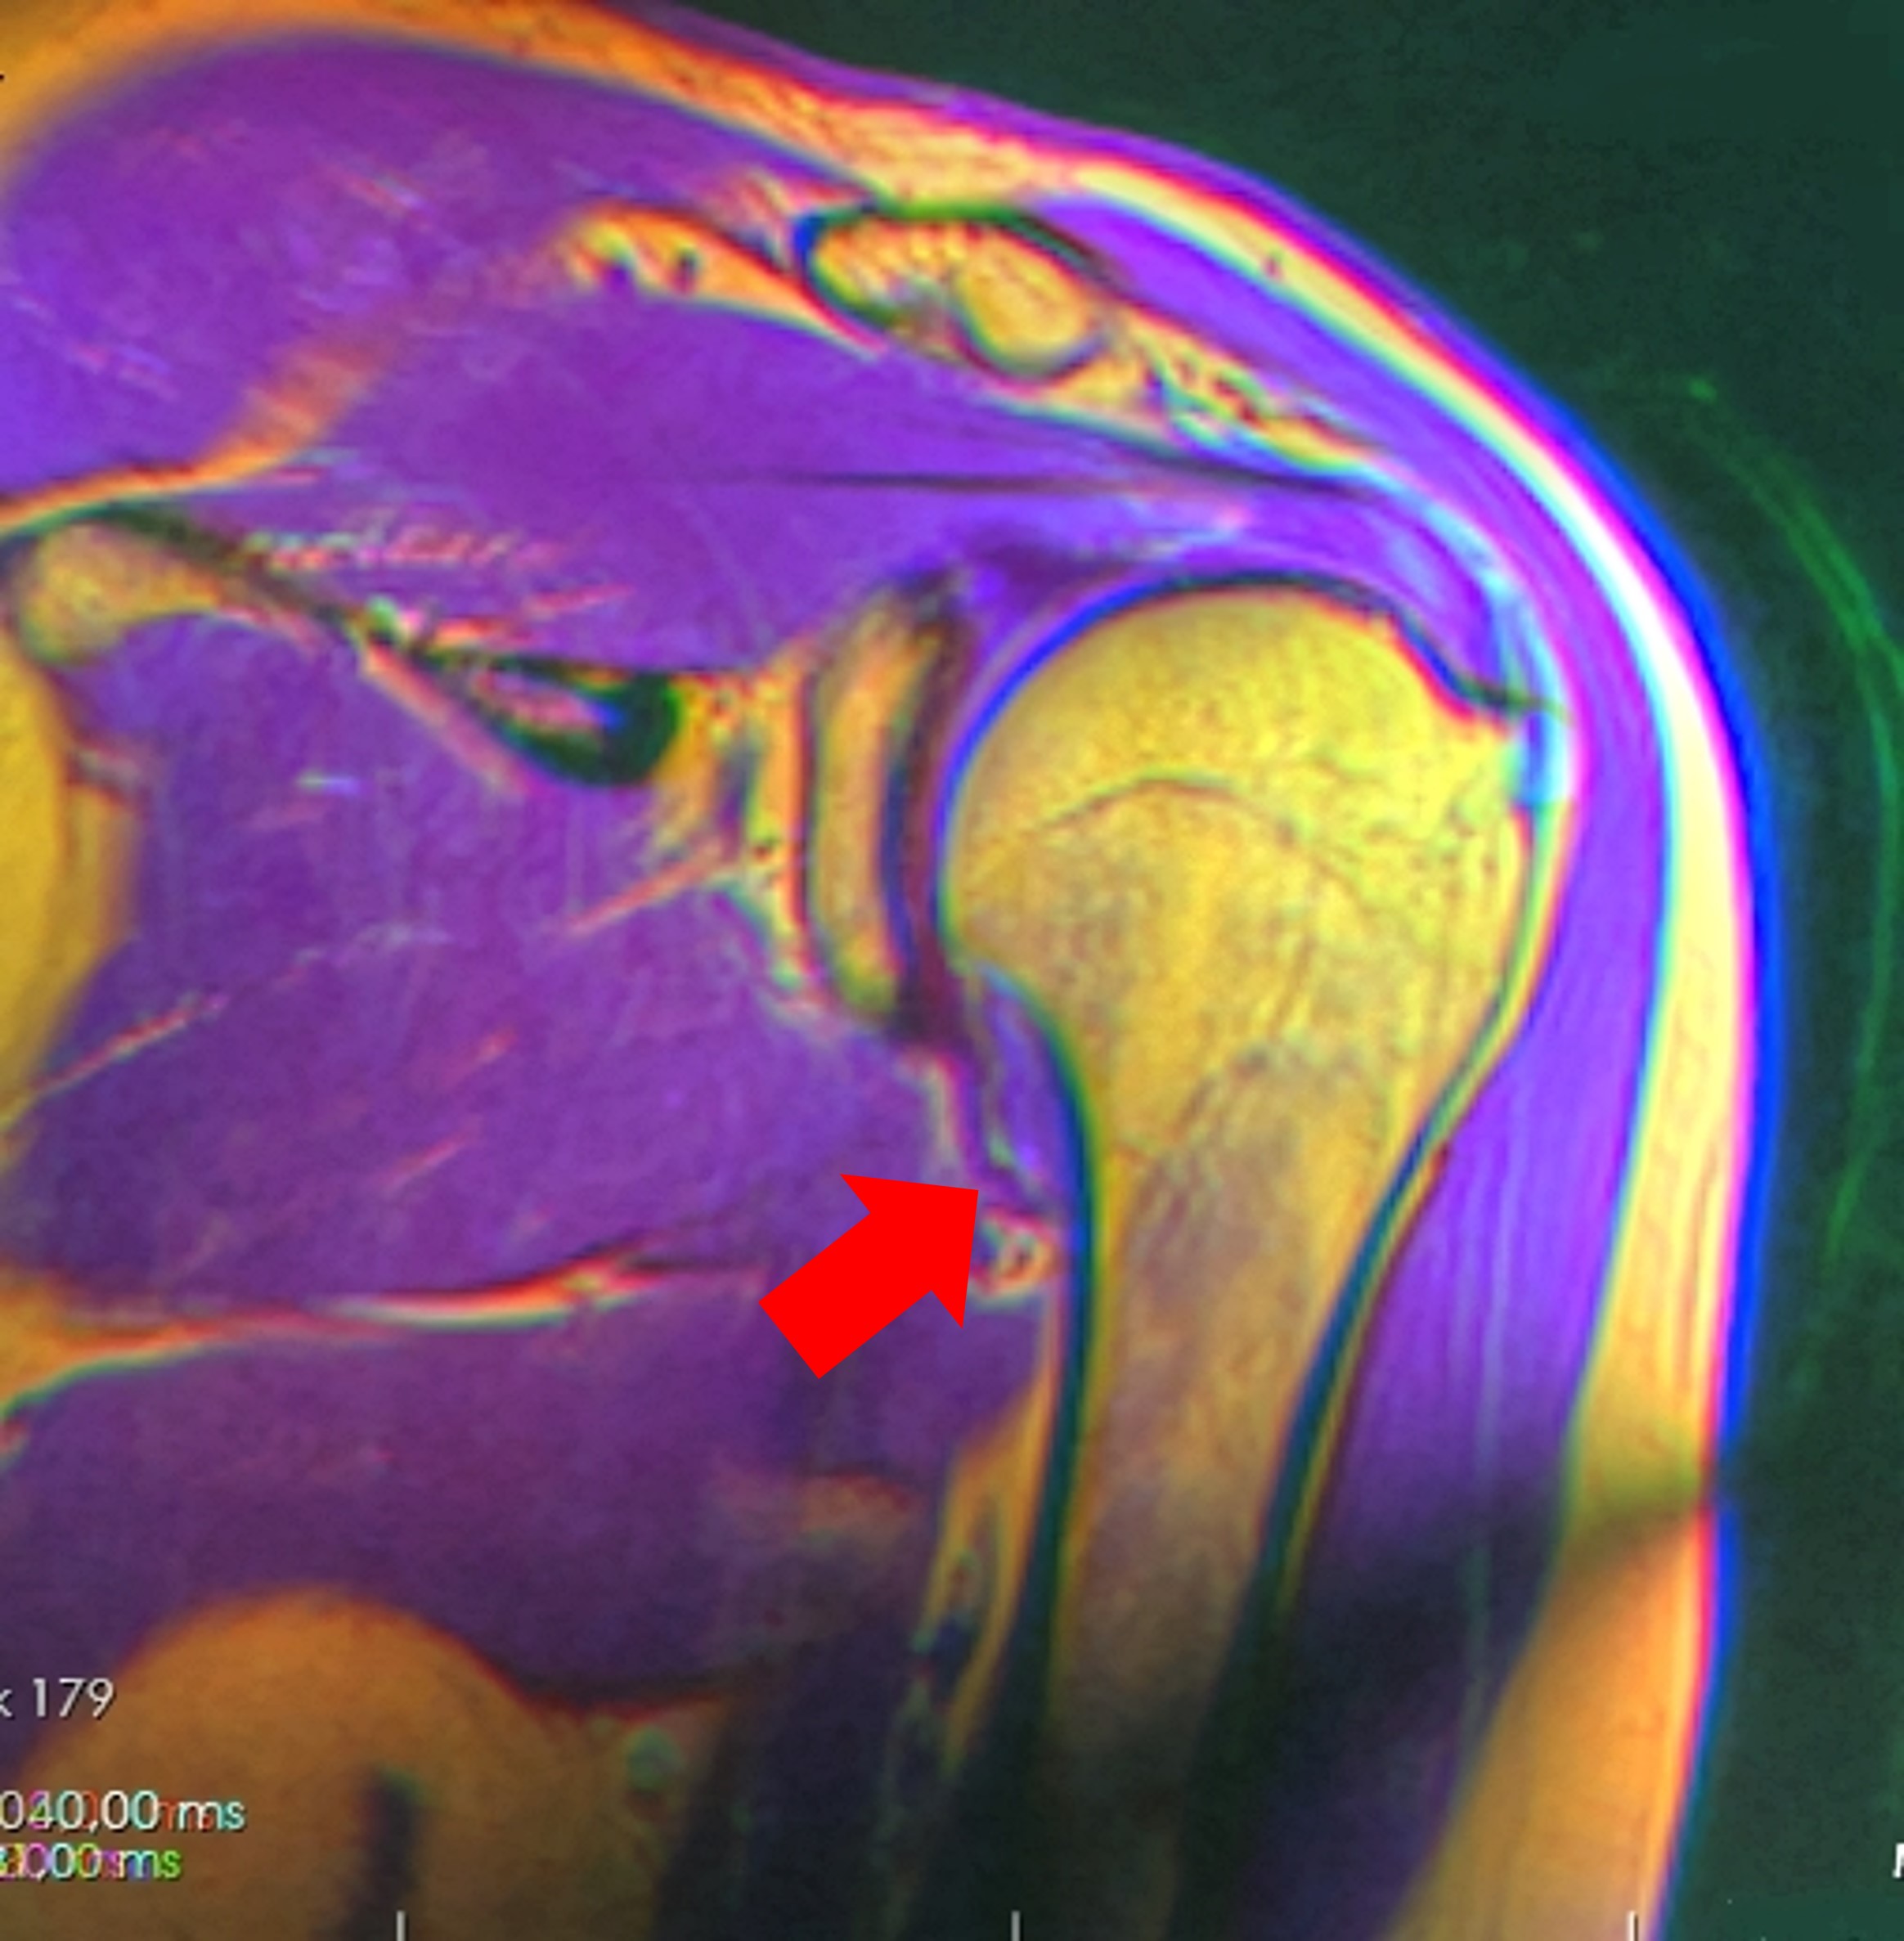

3. MRI :

사실상 동결견을 진단하는데 가장 중요한 진단 방법입니다. MRI는 우리 몸에 있는 물 분자들을 자기장을 이용하여 회전을 주어 그 신호를 이미지로 형상화 하는 기계입니다. X-ray는 X선을 쏴서 발생하는 그림자를 통해 이미지를 만들기에 뼈가 아닌 연부조직들, 즉 근육이나 인대, 관절낭 등은 이미지화 시킬 수가 없다는 점이 한계이지만, MRI는 이러한 연부조직 들 모두 수분을 가지고 있기에 이미지화 할 수 있는 장점이 있습니다.

오십견이 의심되는 환자에서 MRI를 찍는 이유는 앞서 말씀드린 관절낭이 얼마나 질겨졌는지를 확인하기 위한 것입니다.

오십견에서는 관절낭의 섬유화가 만성적으로 진행되었기 때문에, 관절낭 주머니의 두께가 일반사람보다 상당히 비후된 것을 확인할 수 있습니다. (4mm 이상인 경우 진단 가능) 특히 오십견 환자에서 제한되는 내회전과 전방거상, 외회전등에 중요하게 관여하는 액와주변 관절낭과 그 주변 인대조직들의 비후를 관찰 할 수 있습니다.

또한 이차성 동결건의 원인이 될 수 있는, 석회성 건염, 회전근개 증후군 및 파열 등을 진단하는데에도 MRI는 아주 효과 적인 검사 방법입니다.